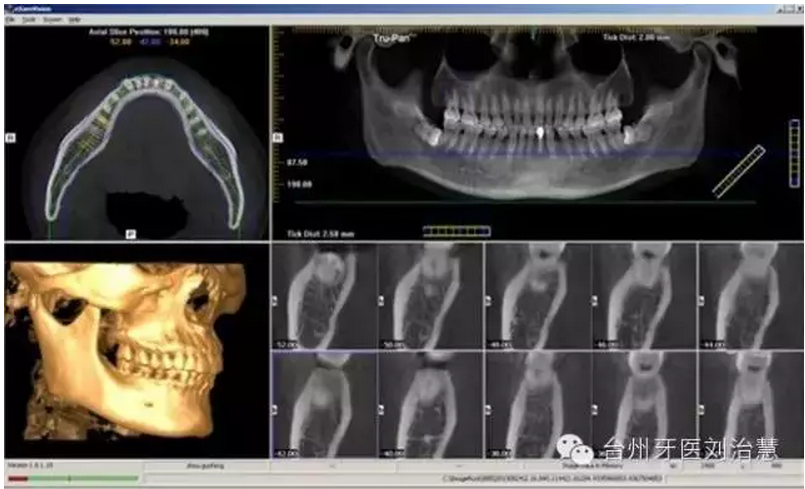

口腔CT,指的是CBCT,就是Cone beam

CT的簡(jiǎn)稱,即錐形束CT。顧名思義是錐形束投照計(jì)算機(jī)重組斷層影像設(shè)備,其原理是X線發(fā)生器以較低的射線量(通常球管電流在10毫安左右)圍繞投照體做環(huán)形DR(數(shù)字式投照)。然后將圍繞投照體多次(180次-360次,依產(chǎn)品不同而異)數(shù)字投照后“交集”中所獲得的數(shù)據(jù)在計(jì)算機(jī)中“重組,reconstruction”后進(jìn)而獲得三維圖像。

CBCT與體層CT(螺旋CT)的最大區(qū)別在于體層CT的投影數(shù)據(jù)是一維的,重建后的圖像數(shù)據(jù)是二維的,重組的三維圖像是連續(xù)多個(gè)二維切片堆積而成的,其圖像金屬偽影較重。而CBCT的投影數(shù)據(jù)是二維的,重建后直接得到三維圖像。從他們的成像結(jié)構(gòu)看,CBCT用三維錐形束X線掃描代替體層CT的二維扇形束掃描;與此相對(duì)應(yīng),CBCT采用一種二維面狀探測(cè)器來(lái)代替體層CT的線狀探測(cè)器。

顯然,CBCT采用錐形束X線掃描可以顯著提高X線的利用率,只需旋轉(zhuǎn)360度即可獲取重建所需的全部原始數(shù)據(jù)。因此,患者接受射線大大減少。

CBCT卓越的清晰度和細(xì)節(jié)顯示根尖、牙冠、切端和上頜竇等各個(gè)解剖結(jié)構(gòu)。對(duì)特定解剖結(jié)構(gòu)的智能重建能夠?yàn)槊课换颊咦詣?dòng)創(chuàng)建最優(yōu)的個(gè)性化圖像。

能夠以DICOM格式保存并輸出掃描數(shù)據(jù),便于臨床醫(yī)生使用各種3D設(shè)計(jì)軟件。當(dāng)使用第三方軟件制定治療計(jì)劃時(shí),這個(gè)新工具可以大大加快工作流程,對(duì)于忙碌的牙科診療過程特別重要。